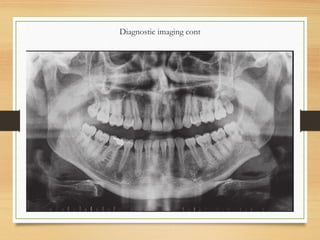

Diagnostic imaging cont

• Orthopanthomogram